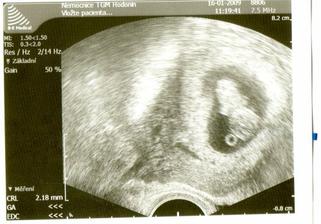

Tak 29.12. je pro mě šťastný den.Na ultrazvuku potvrzeno těhotenství.Mimísek byl krásně vidět a dokonce už tlouklo i srdičko.Dle ultrazkuku jsem 6+3.Takže ovulka byla později.Obrečela jsem to.Tak snad už bude vše OK.Děkuji všem,kteří mě drželi pěsti.**************************2.1.2009 začalo pobolívat bříško,tak jsem zůstala v nemocnici.Mimi se má k světu.5.12. jsem byla na ultrazvuku jsme 8 tt a máme 1,25 cm.To je macek,že?6.1.2009 jsem byla propuštěná z nemocnice.Konečně doma.Máme neschopenku a prý už na celé těhu.Na další kontrolu jdu 20.1. v 9 hodin.Už teď se bojím,aby bylo vše vpořádku.Jsem asi blázen.*************************************************